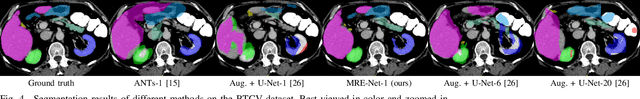

Abstract:Medical image segmentation has achieved remarkable advancements using deep neural networks (DNNs). However, DNNs often need big amounts of data and annotations for training, both of which can be difficult and costly to obtain. In this work, we propose a unified framework for generalized low-shot (one- and few-shot) medical image segmentation based on distance metric learning (DML). Unlike most existing methods which only deal with the lack of annotations while assuming abundance of data, our framework works with extreme scarcity of both, which is ideal for rare diseases. Via DML, the framework learns a multimodal mixture representation for each category, and performs dense predictions based on cosine distances between the pixels' deep embeddings and the category representations. The multimodal representations effectively utilize the inter-subject similarities and intraclass variations to overcome overfitting due to extremely limited data. In addition, we propose adaptive mixing coefficients for the multimodal mixture distributions to adaptively emphasize the modes better suited to the current input. The representations are implicitly embedded as weights of the fc layer, such that the cosine distances can be computed efficiently via forward propagation. In our experiments on brain MRI and abdominal CT datasets, the proposed framework achieves superior performances for low-shot segmentation towards standard DNN-based (3D U-Net) and classical registration-based (ANTs) methods, e.g., achieving mean Dice coefficients of 81%/69% for brain tissue/abdominal multiorgan segmentation using a single training sample, as compared to 52%/31% and 72%/35% by the U-Net and ANTs, respectively.